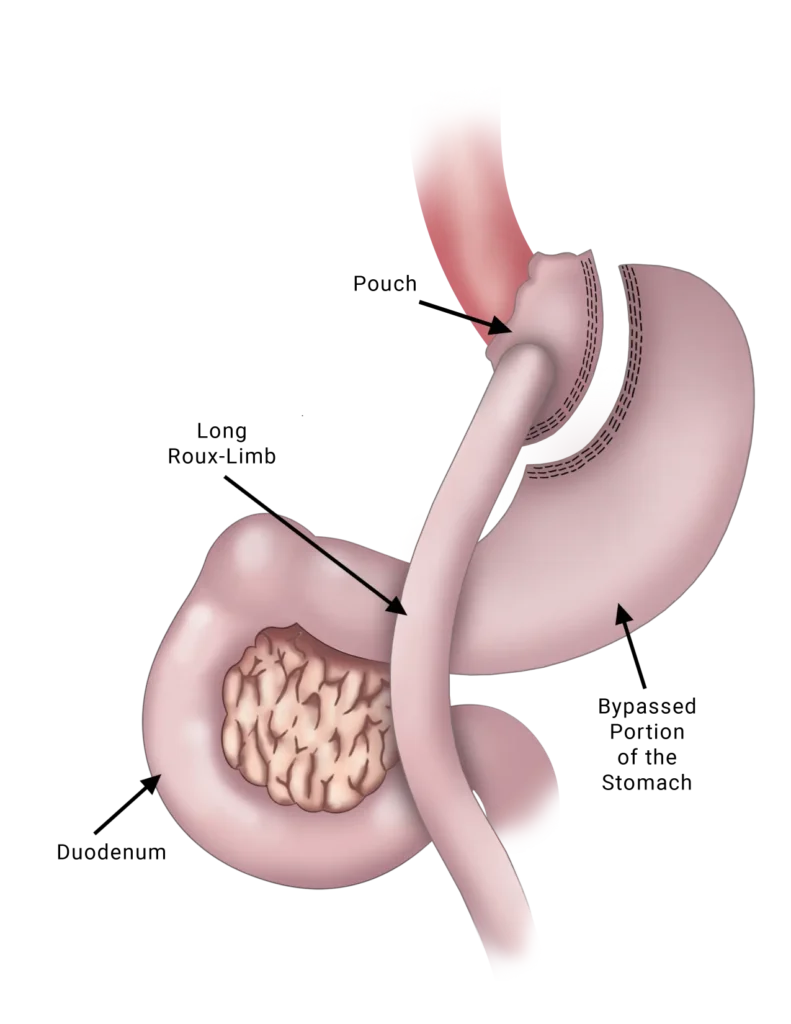

Laparoscopic Gastric Bypass Surgery